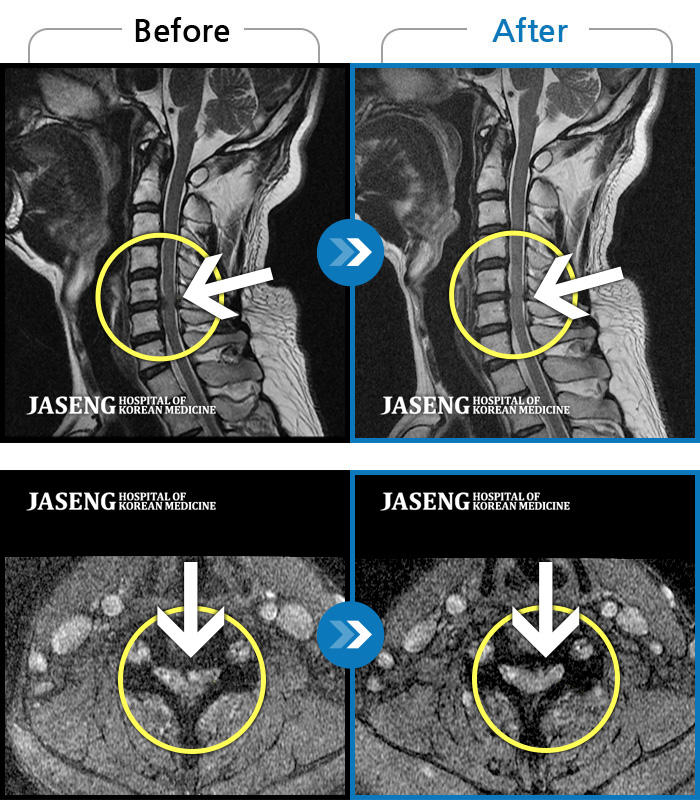

목디스크때문에 고개를 돌리지도 못하고 팔이 많이 저렸는데 진은석 원장님에게 봉침과 추나를 3개월 정도 받고 완전히 괜찮아졌어요. 정말 감사합니다.